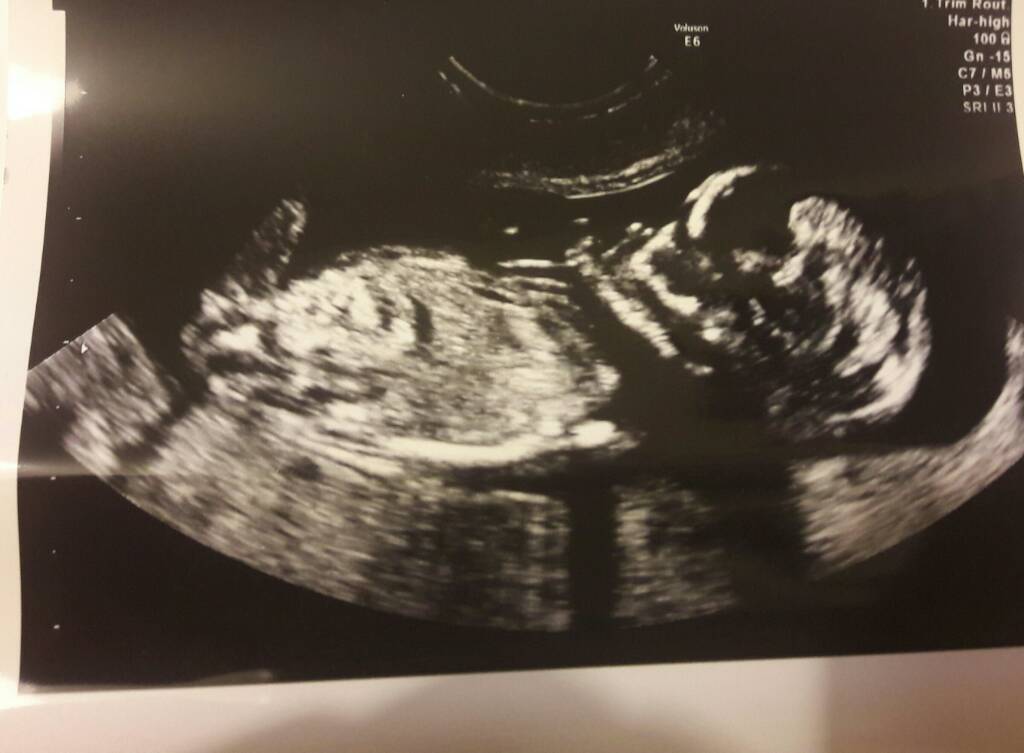

gratuluję udanej wizytyHej dziewczyny! Wpadłam tylko na chwilę, bo muszę popisać pracę na zaliczenie na studiach. Chciałabym pochwalić się Wam, że byłam wczoraj u mojej gp. Z dzidziusiem wszystko ok, posłuchałyśmy serduszka, 140 biłopięknie skakało i machało kończynami

Niestety pani doktor nie zmierzyło go

płci też nie podała, bo podobno za słaby sprzęt. Za 3 tygodnie połówkowe 3d, więc mam nadzieję, że już będę wiedziała, kto tam siedzi. Była ze mną mama, bo sama nie miała nigdy usg w ciąży. Strasznie się wzruszyła